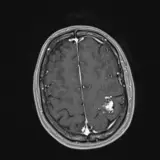

Over 2,100 interactive radiology cases, curated by radiologists for your level of training. Scroll, window, and view cases full screen — just like on PACS. Click linked findings in each writeup to jump straight to them on the image. Cases include sample reports, a focused discussion section, original illustrations, and videos.

Des cas entièrement interactifs avec les outils attendus d'un PACS — défilement, fenêtrage, zoom, déplacement, mesures, ROI et mode plein écran.

Des annotations détaillées mettent en évidence les résultats clés directement sur les cas. Cliquez sur les résultats liés dans les descriptions de cas pour accéder à leur emplacement exact sur l'examen.